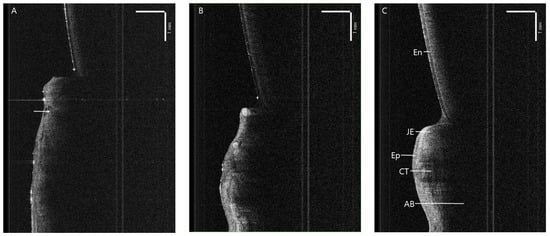

3.3.1. Apically Positioned Flap

Laser

Scalpel